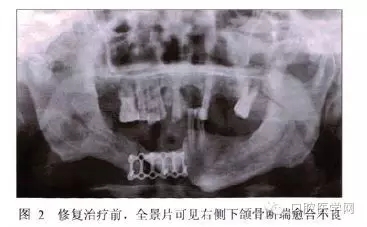

全景片示:下頜骨右側(cè)有不透光骨固定物,斷端結(jié)合處有透光影,余留牙處略有骨吸收,根尖周未見明顯異常(圖2)。